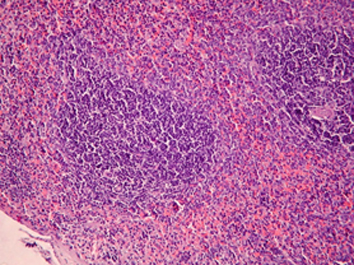

Результаты. Показано, что применение рифабутина в сочетании с аскорбигеном приводит к ослаблению повреждающего действия антибиотика на слизистую оболочку желудочно-кишечного тракта и ускорению процессов восстановления ее структуры, что клинически выражается в нормализации прироста массы тела животных. При комбинированном применении рифабутина с аскорбигеном уменьшается глубина цитопении, а количество лейкоцитов в периферической крови крыс восстанавливается быстрее. Признаки атрофии лимфоидной ткани селезенки отсутствуют. Введение аскорбигена до рифабутина оказывает протекторный эффект в отношении тканей почек и семенников.